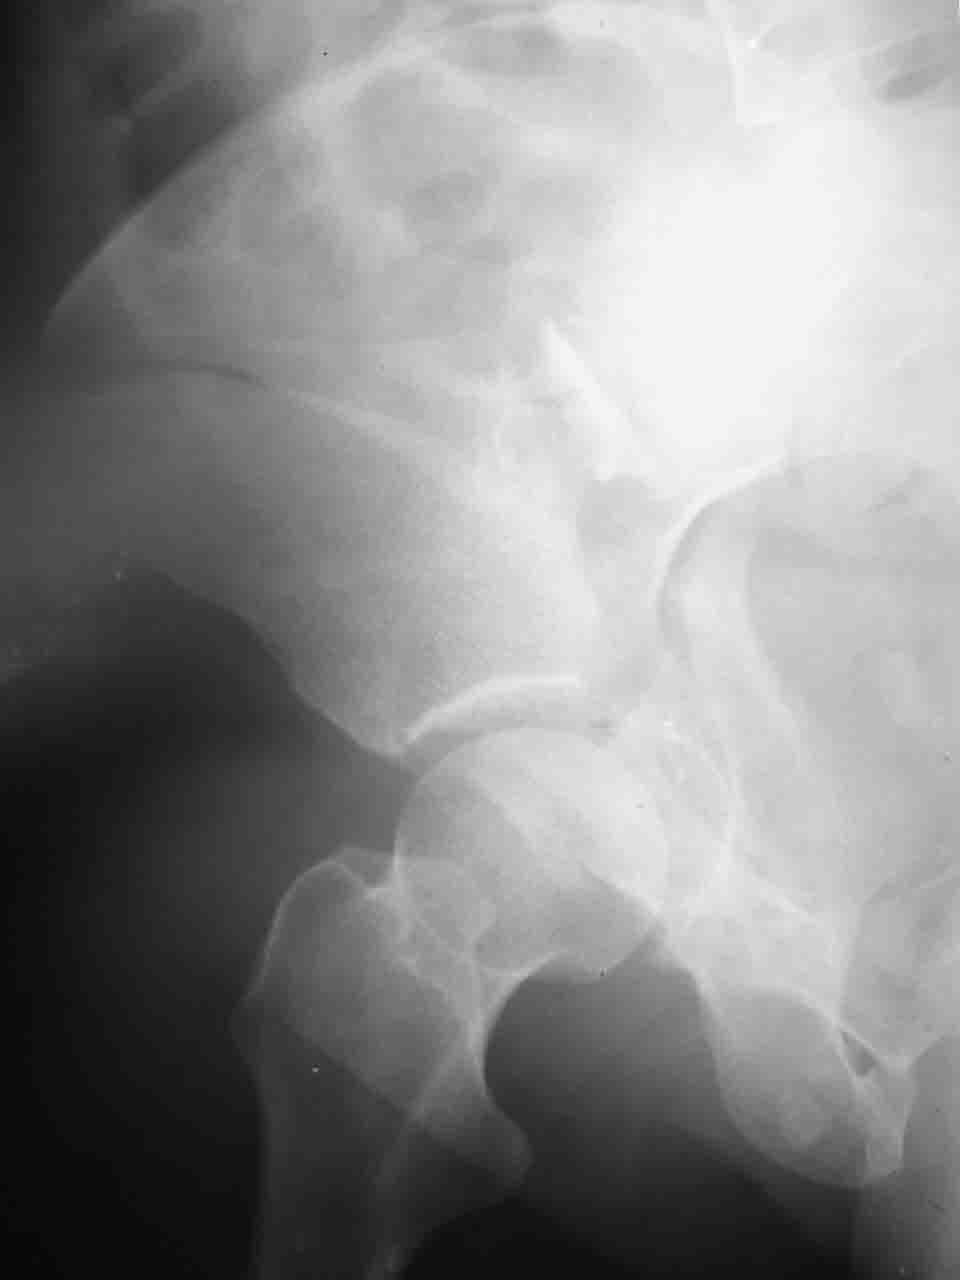

Re: Перелом вертлужной впадины

Спасибо за комментарии и рекомендации. Откровенно говоря, больного я прооперировал на прошлой неделе, через 5 дней после аварии и проблем с ним пока никаких нет, на удивление при достаточно обширной диссекции (илиофеморальный доступ) болей практически нет, так что больной самостоятельно садится в кровати, выполняет активные движения в оперированном суставе, сгибая до 60 градусов пока, далее с ассистенцией.

Причиной обращения к сообществу были возникшие непосредственно после операции сомнения и разочарования полученным качеством репозиции: а надо ли было трогать перелом вообще, репозиция передней колонны технически была очень сложна для меня, хотя реконструкции была в той же последовательности, что Д-р А.В.Рунков рекомендовал, в какой-то момент безуспешных манипуляций стал думать о *вторичной конгруэнтности*, которую не так давно обсуждали на

форуме и скелетном вытяжении. С репозицией и фиксацией задней колонны и отдельно задне-верхней стенки впадины проблем не возникло. Послеоп. Рг граммы в приложении. Если возникнут какие-либо дополнения или поправки - был бы признателен.